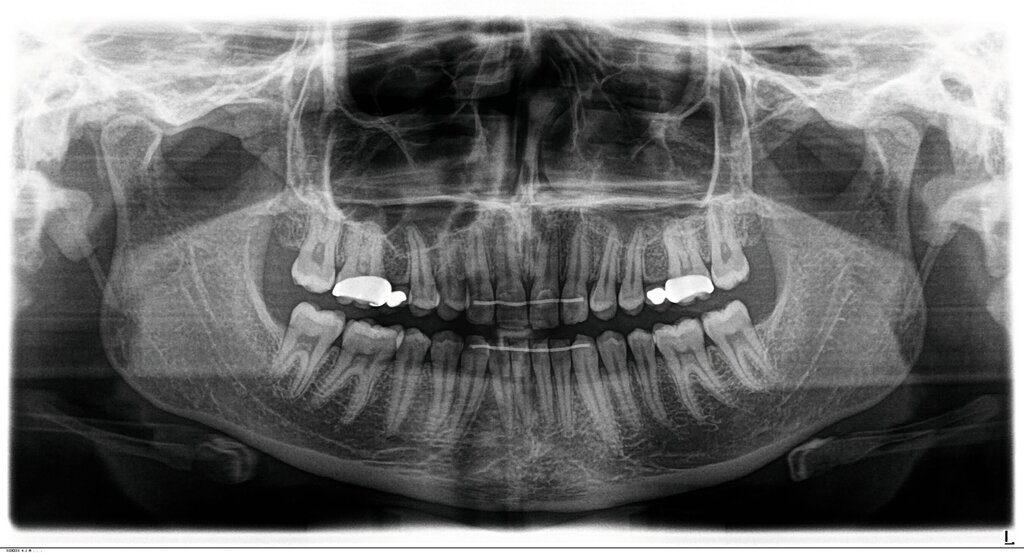

Bei dem gut zwölfjährigen Mädchen sind die seitlichen oberen Schneidezähne (Zähne 12 und 22) nicht angelegt. Zusätzlich zeigten sich verlagerte zweite obere Prämolaren.

Im vorliegenden Fall stand der Zahn 23 bereits im Mesialstand bei hoher Lachlinie und tendenziell konkavem Lippenprofil. Bezüglich Morphologie und Farbe waren die Zähne 13 und 23 nicht ausgeprägt eckzahntypisch. Es bestand kein Platzmangel im Gegenkiefer. Die Patientin war bei der Erstdiagnose 12,5 Jahre alt und im Wechselgebiss der zweiten Phase mit atypischer Durchbruchreihenfolge. Es bestand eine geringfügige Klasse II. Der Overjet war vergrößert bei vertikaler Wachstumstendenz, der Overbite war um circa einen Millimeter vergrößert aufgrund der geringfügigen Steilstellung der Oberkiefer-Front. Es bestand der Verdacht auf Nichtanlage der Weisheitszähne, 15 und 25 waren verlagert.